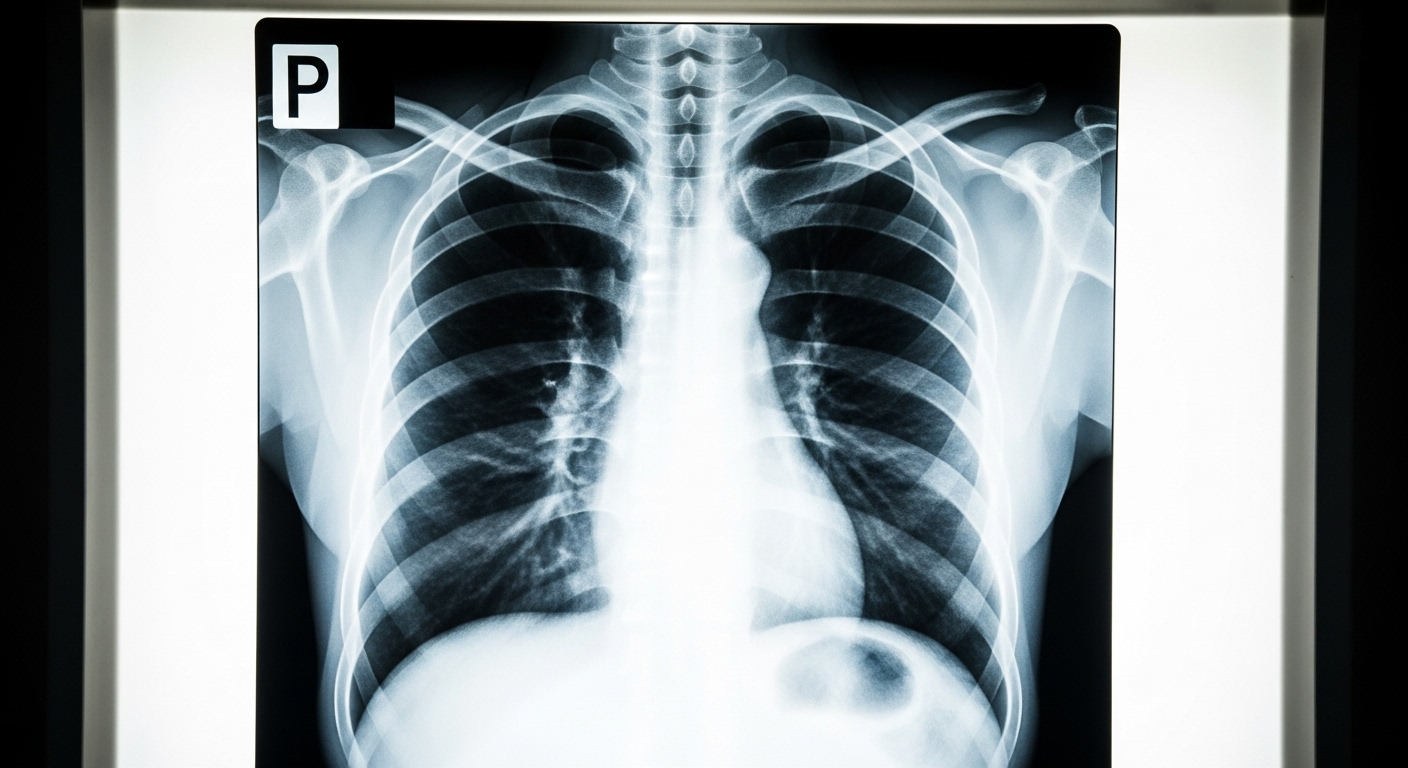

Đơn giản mà nói, tia X là một dạng bức xạ điện từ có khả năng xuyên qua các mô mềm của cơ thể như da, cơ. Khi đi qua xương hoặc các mô đặc như khối u, tia X sẽ bị cản lại nhiều hơn. Sự khác biệt về mật độ này sẽ tạo ra các vùng sáng, tối khác nhau trên phim, giúp chúng ta nhìn thấy hình ảnh bên trong.

Phổi của chúng ta chứa đầy không khí, nên trên phim X-quang thường có màu đen hoặc rất tối. Các mạch máu, tim và xương sườn sẽ hiện lên màu trắng sáng hơn. Chính nhờ sự tương phản này mà bác sĩ có thể nhận diện những dấu hiệu bất thường.

Trên phim X-quang, những vùng tổn thương do viêm phổi hay viêm phế quản thường hiện rõ dưới dạng thâm nhiễm, đông đặc trong nhu mô phổi. Đôi khi, các triệu chứng ban đầu chỉ là ho nhẹ, mệt mỏi, hoặc sốt thoáng qua, rất dễ bị bỏ qua.

Tuy nhiên, hình ảnh X-quang thường có thể cho thấy những tổn thương đặc trưng như hang lao, các nốt mờ nghi ngờ. Phát hiện sớm bệnh lao qua X-quang không chỉ giúp người bệnh được điều trị hiệu quả mà còn có ý nghĩa to lớn trong việc hạn chế sự lây lan trong cộng đồng.

Đây là điều mà chúng ta lo sợ nhất, và cũng là lúc chụp X-quang phát huy vai trò quan trọng của nó. Kỹ thuật này có khả năng phát hiện những tổn thương nhỏ trong nhu mô phổi, đôi khi kích thước chỉ từ vài milimet đến vài centimet.

Trên hình ảnh X-quang tràn dịch, bác sĩ sẽ thấy vùng mờ ở đáy phổi, làm tù góc sườn hoành vốn nhọn. Còn đối với tràn khí, sẽ thấy vùng phổi bị xẹp lại, cùng với một khoảng sáng bất thường trong lồng ngực. Những tình trạng này có thể do viêm nhiễm, chấn thương, bệnh phổi mạn tính hoặc các bệnh lý ác tính khác.

Chẳng hạn như phổi tăng sáng, phế trường giãn rộng, hoặc các vùng xơ hóa. Phát hiện sớm qua X-quang giúp người bệnh có kế hoạch điều trị, thay đổi lối sống và theo dõi lâu dài để làm chậm tiến triển của bệnh.

Đừng quên rằng một tấm phim X-quang ngực không chỉ cho chúng ta thấy phổi mà còn cung cấp cái nhìn tổng quát về tim và các cấu trúc xương lồng ngực. Nó có thể giúp nhận diện dấu hiệu tim to, biến dạng lồng ngực, hoặc các bất thường ở xương sườn, cột sống ngực.